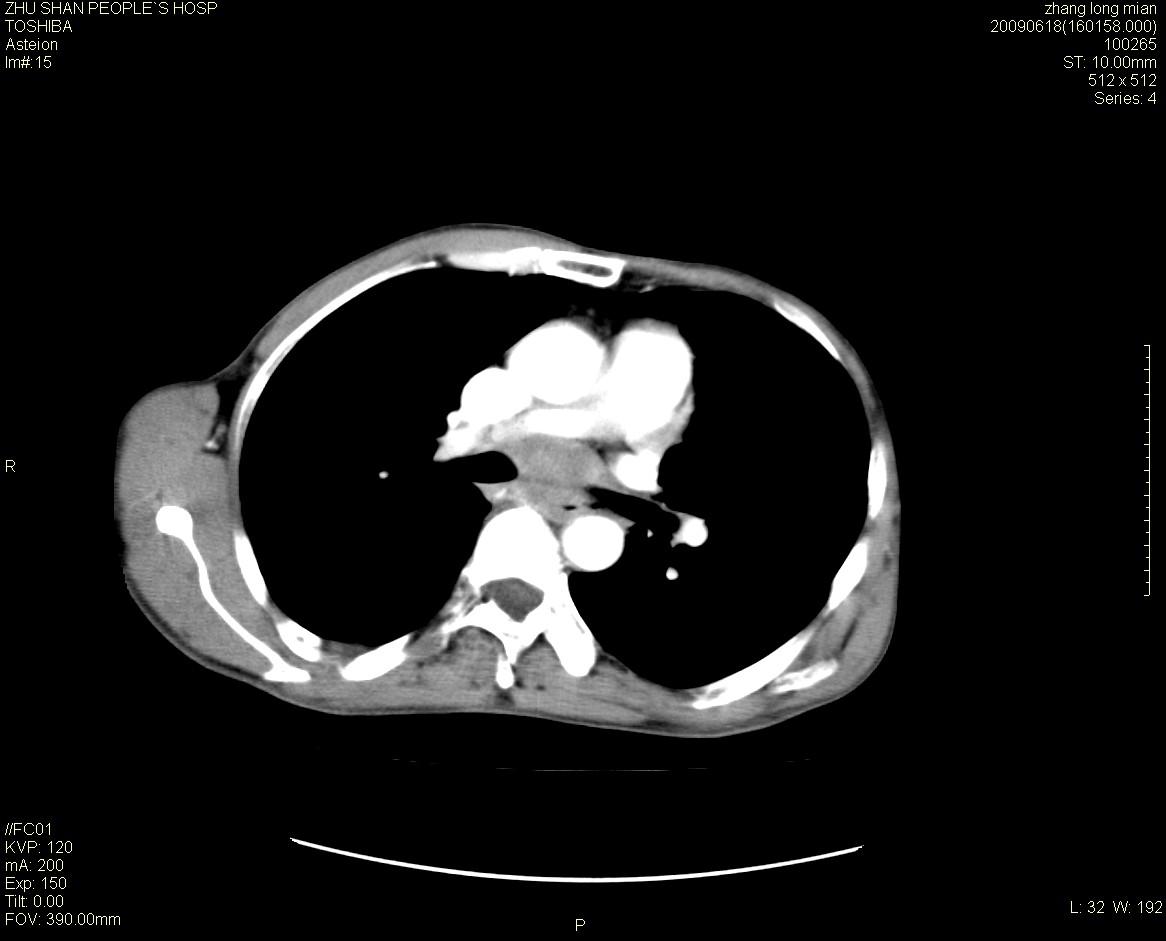

男性 65岁 胸片发现右下肺包块.诊断肺ca并纵隔转移没有问题吧!

肺ca并纵隔转移,阻塞性炎症。

两侧胸廓不对称,右侧呈塌陷改变,右肺萎缩。

右下肺见浅分叶状软组织块影,边缘有毛刺,其下部似见不完整偏心空洞影,邻近胸膜凹陷征,并胸腔积液。

增强见纵隔区气管隆突上下及左肺门区肿大淋巴结。左肺感染性病灶。

另见右上肺见一枚小结节影,性质待定。